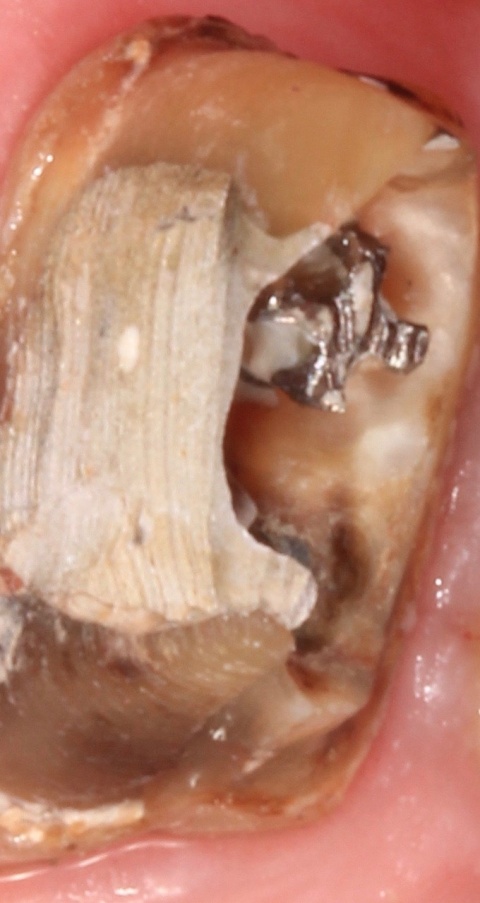

Nach ausführlicher Aufklärung der vorhandenen Therapiealternativen entschied sich der Patient für die Revisionsbehandlung. Diagnostisch wichtig war in diesem Fall die Bestimmung des inserierten Wurzelstiftes. Röntgenologisch unterscheiden sich Glasfaser- und Metallstifte aufgrund der physikalischen Eigenschaften des Materials deutlich, sodass es sich hier zweifelsfrei um einen Metallstift handelte. Durch das röntgenologisch sichtbare Gewinde ließ sich die Art des Stiftes bestimmen. So war nach Entfernen der Krone das vorsichtige Freischleifen des Stiftkopfes (Abb. 6) wichtig, um den Stift mit einem speziellen Schlüssel ausdrehen zu können (Abb. 7).

Zu diesem Zeitpunkt war der Zahn noch provisorisch mit Cavit® und einer Schicht Komposit verschlossen. Der Perkussionstest verlief negativ, jedoch zeigte sich noch eine Lockerung Grad I. Im Bereich des Vestibulums war weder eine Schwellung sicht- oder tastbar und dieser Bereich wies keine Druckdolenz auf. Ein Grund für diese Abszedierung kann in einer Traumatisierung des Gewebes durch die Kofferdamklammer mit einer bakteriellen Besiedlung zu sehen sein. Nach Infiltrationsanästhesie wurde der Abszess inzidiert und mit einer Povidon-Jod-Lösung (Betaisadona®, ADAG Pharma) gespült. Für eine Woche wurde adjuvant eine Antibiotikagabe verordnet (Clindamycin 400 mg). Vier Tage nach Inzision wurde der Patient zur Kontrolle einbestellt. Zu diesem Zeitpunkt war er beschwerdefrei und die Schwellung deutlich regredient. Im Rahmen dieser Nachkontrolle erfolgte die Entfernung der provisorischen Deckfüllung und eine Inspektion des Pulpencavums auf Risse oder Blutungen (Abb. 9). Diese Untersuchung fiel ohne pathologischen Befund aus, woraufhin eine definitive Deckfüllung appliziert werden konnte.